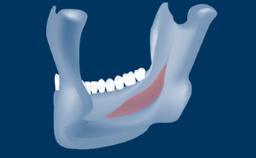

• intraoperative complications of lateral window sinus floor elevation

• intraoperative complications of transcrestal sinus floor elevation

• postoperative complications of sinus floor elevation